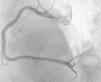

Obteve-se sucesso da angioplastia de balão, sem lesão residual e com fluxo final TIMI 3 (Figura 3).